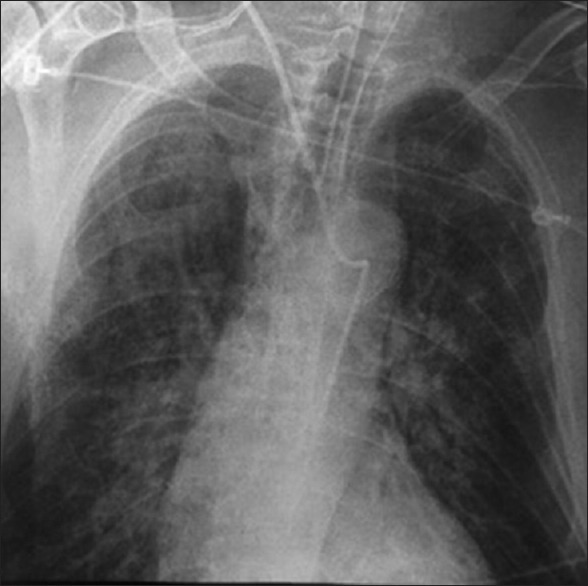

You are called to the PACU to evaluate a patient in whom you have just placed a tunneled venous access device. The post-procedure chest radiograph demonstrates a port in the right chest region with the catheter tracking underneath the right clavicle, crossing the midline and descending down the left side of the mediastinum. What is your initial work-up? What is the most appropriate treatment?